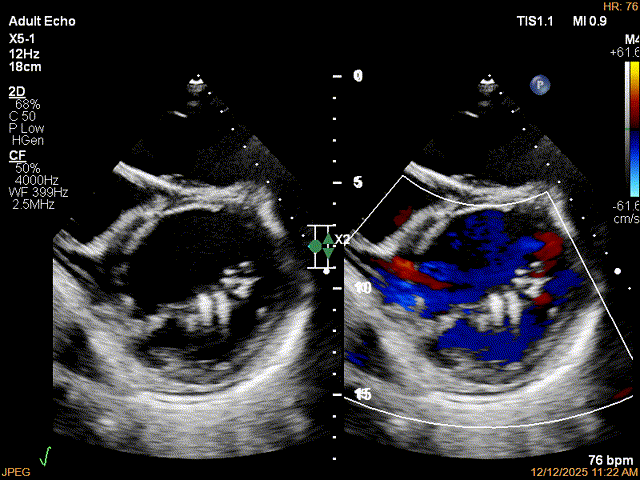

患者食道胃底静脉曲张,遂行TTE术前评估

术前TTE评估:

MR反流病因:DMR(部分腱索断裂)、Carpentier II型;

反流程度:极重度(5+),PISA法估测EROA约1.12cm²,R-VOL约98ml;

病变情况:P2-部分P3,脱垂宽度约27mm ,连枷间距11-13mm,瓣口面积7.8cm²,PML约25mm

其他:TR(重度) ,间接估测PASP约65mmHg;

预估手术难点:后叶冗长,脱垂宽度大,连枷间距大。